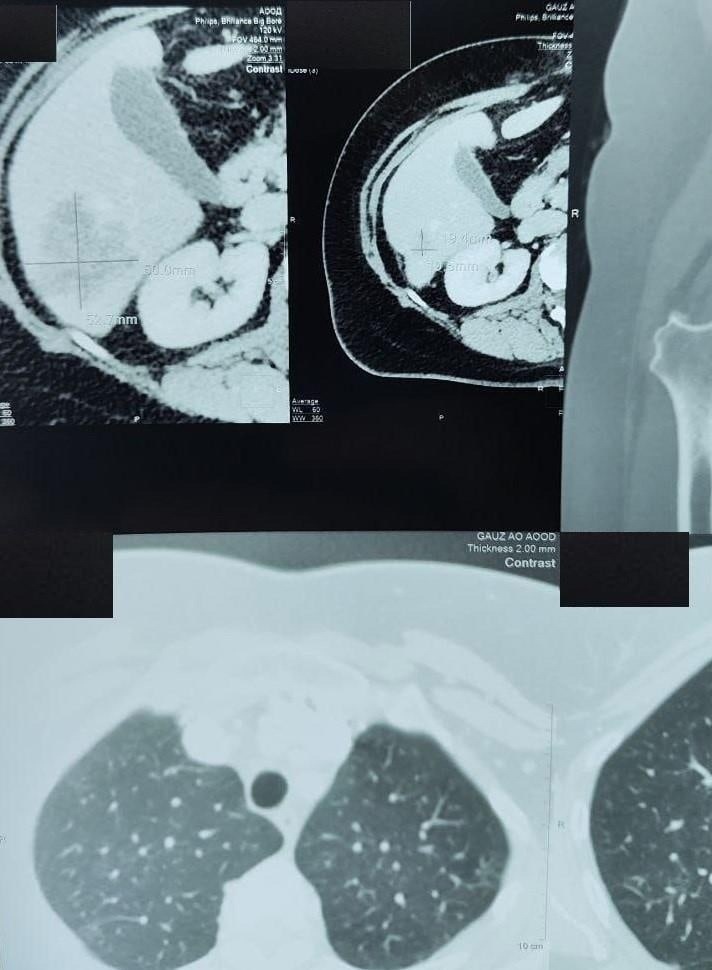

Амурчанка обратилась в диспансер в сентябре 2023 года с диагнозом рак селезёночного изгиба ободочной кишки с метастазом в печени. Врачи разработали комплексный подход к лечению, включающий в себя несколько этапов борьбы с опухолью.

В результате контрольных исследований специалисты установили, что опухоль уменьшилась на 60 %, а гистологическое исследование подтвердило полный лечебный регресс опухоли.